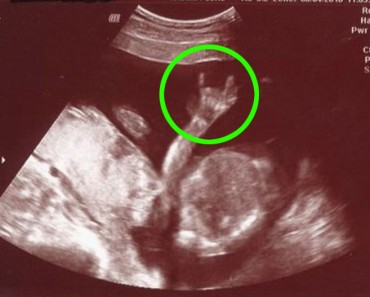

El increíble momento en el que un bebé es captado aplaudiendo en el útero de su madre